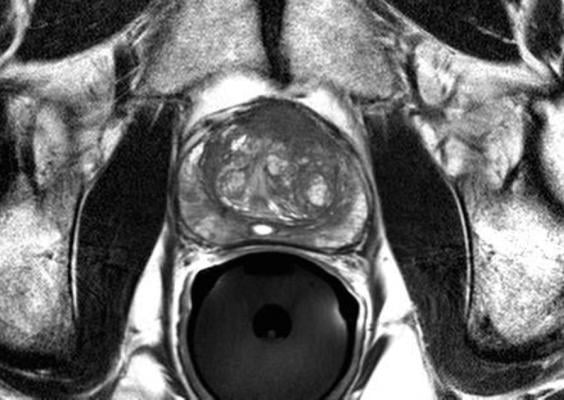

MRI technology is a precise tool that could better identify which patients should undergo biopsy, and enable targeted biopsy of only areas suspected of malignancy. The PRECISE trial, which is estimated to be completed in three years, will investigate the ability of MRI to improve the diagnosis of clinically important disease and reduce the requirement for prostate biopsies.

Currently, prostate cancer is diagnosed by trans-rectal ultrasound (TRUS)-guided biopsy of the prostate, in most cases following a prostate specific antigen (PSA) test. TRUS-guided biopsy is associated with potential side effects such as infection and bleeding because it is not targeted, requiring numerous biopsy samples (between 10 and 12) to establish an accurate reading. In addition, this current standard of care is not sensitive enough to be able to discriminate between high-risk and very low-risk changes in prostate tissue, resulting in the over-diagnosis and over-treatment of many men, exacerbating the risk for side effects.